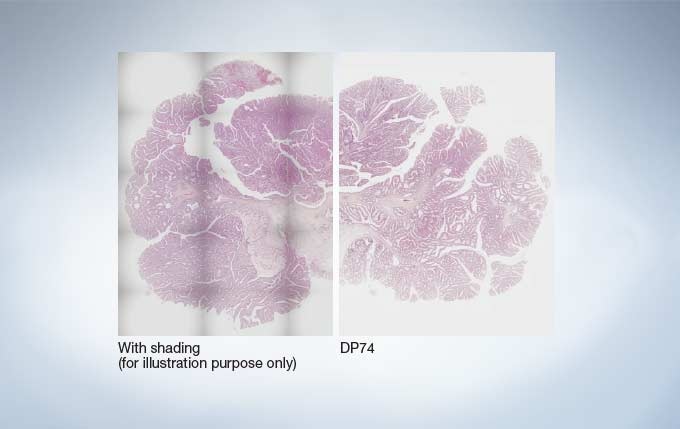

Seamless Stitching with Even Illumination Across the Image

With the shading correction feature, it’s possible to produce beautiful macro images with fewer seams. Tiling is faster thanks to the wider field of view and the fast frame rate, leading to beautiful macro images.